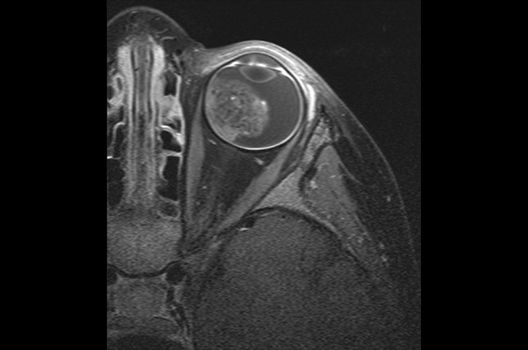

Magnetresonanztomographie

- Hochaufgelöste MR-Bildgebung (HR-MRT)

- Arterielle und venöse Angio-MRT

- MR-Protonenspektroskopie

- Funktionelle Bildgebung des Gehirns (fMRT)

- MR-Diffusionstensorbildgebung (Faserbahndarstellung/fiber tracking)

Die Schwerpunkte in der MR-Forschung liegen in der multiparametrischen und funktionellen Bildgebung bei onkologischen und anderen, neuroradiologischen Fragestellungen und umfassen die Anwendung modernster MR-Verfahren sowie die Untersuchung an Hochfeld-Geräten.

Die Magnetresonanztomographie (MRT) ist ein Verfahren, bei dem durch magnetische Kräfte Bilder des Körperinneren angefertigt werden. In der Neuroradiologie können manchmal kleinste Veränderungen schwere Folgen haben; daher forschen wir an der Entwicklung hochauflösender MRT-Sequenzen, mit denen diese Prozesse und auch einzelne Nervenfaserbahnen sichtbar gemacht werden können. Darüber hinaus sind bei vielen Erkrankungen des Gehirns die Blutgefäße betroffen. Daher arbeiten wir an der Neu- und Weiterentwicklung von MRT-Sequenzen zur Darstellung der Blutgefäße und zur Blutflussanalyse (sog. „Angio-MRT“). Einen besonderen Forschungsschwerpunkt unserer Klinik stellen die MR-Protonenspektroskopie und die funktionelle MRT dar, mit denen die Analyse einzelner chemischer Substanzen im Hirngewebe oder die Darstellung ausgewählter Hirnfunktionen möglich ist.